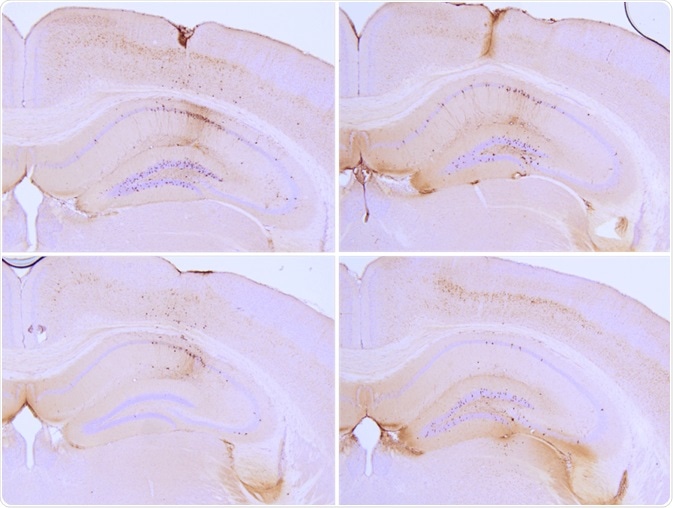

Particular tau PFFs have been injected into P301L mice, where they seed tau aggregation and induce tau pathology in the hippocampus. Fibrils and monomers are available both in the full-length isoform of the tau protein (2N4R or Tau-441) or a truncated form (K18). K18 tau has a molecular weight of approximately 15 kDa, whereas Tau-441 has a molecular weight of around 46 kDa.

Immunohistochemistry analysis of P301L mouse hippocampus injected with K18 P301L tau PFFs (SPR-330) shows seeding of tau pathology at injection site. AT8 (pSer202/pThr205) tau antibody shows tangle-like inclusions. Experiments performed at reMYND N.V.

Immunohistochemistry analysis of P301L mouse hippocampus injected with K18 P301L tau PFFs (SPR-330) shows seeding of tau pathology at injection site. AT8 (pSer202/pThr205) tau antibody shows tangle-like inclusions. Experiments performed at reMYND N.V. Image Credit: StressMarq Biosciences